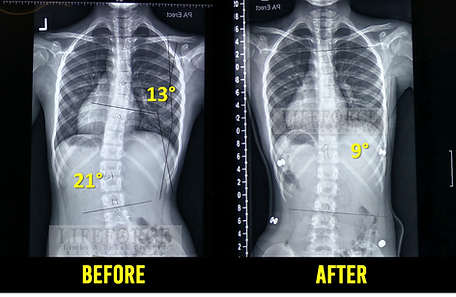

Reliable Support for Teen Spine Care

A scoliosis brace for teenagers is designed to support proper spinal alignment during growth years. Comfortable, adjustable, and discreet, it helps manage posture, reduce curve progression, and fit easily into daily school, study, and activity routines.